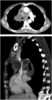

Necrotic lymphadenopathy

Lymphadenopathy or adenopathy is a disease of the lymph nodes, in which they are abnormal in size or consistency. Lymphadenopathy of an inflammatory type (the most common type) is lymphadenitis, producing swollen or enlarged lymph nodes. [Source: Wikipedia ]